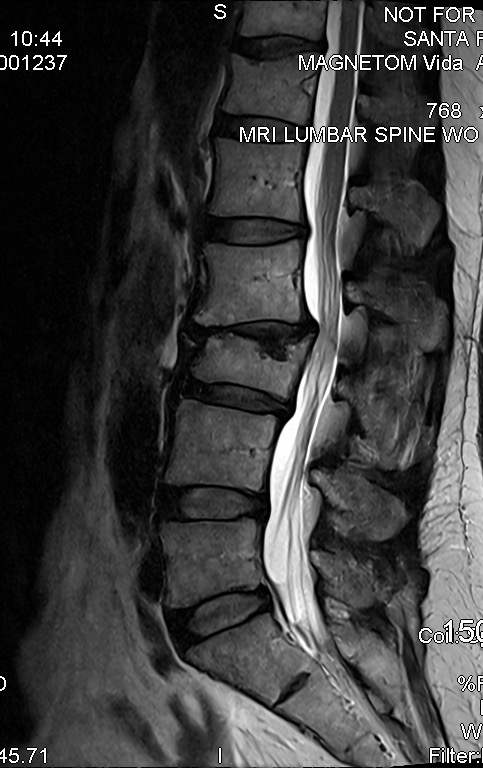

I've broken two of my vertebrae, it's compressing my spinal cord, I have a broken foot, and several broken teeth. It began a cascade of health issues I've dealt with ever since. However, this year, I finally found the right neurosurgeon capable of repairing my broken back. July 11, at UNM Hospital in Albuquerque, I am finally getting the surgery I've waited so long to get. It's a long recovery, but the first few months are going to be the toughest.